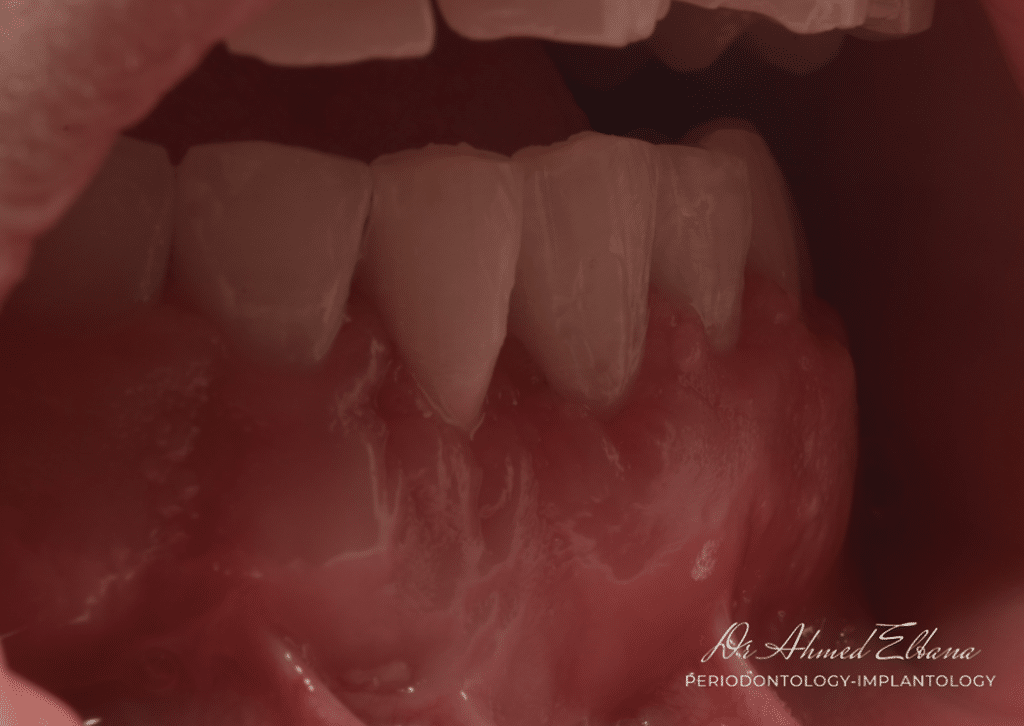

1- Type 2 gingival recession with interproximal CAL loss.

this figure shows:

- gingival recession with root surface exposure.

-lack of attached keratinized gingiva.

-high frenulum pull.